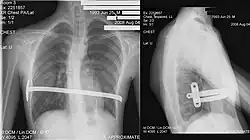

![]() X-Ray of a 15-year-old male after undergoing the procedure | |

Bar removal

After a period of two to four years,[6]: 343 the surgical stainless steel bar is removed from the patient's chest. This procedure lasts approximately ninety minutes. The length of time that the patient stays at the hospital following the bar removal procedure varies, depending on the amount of new bone growth surrounding the bar. Accordingly, the length of time may range from a few hours to several days, or up to one week.